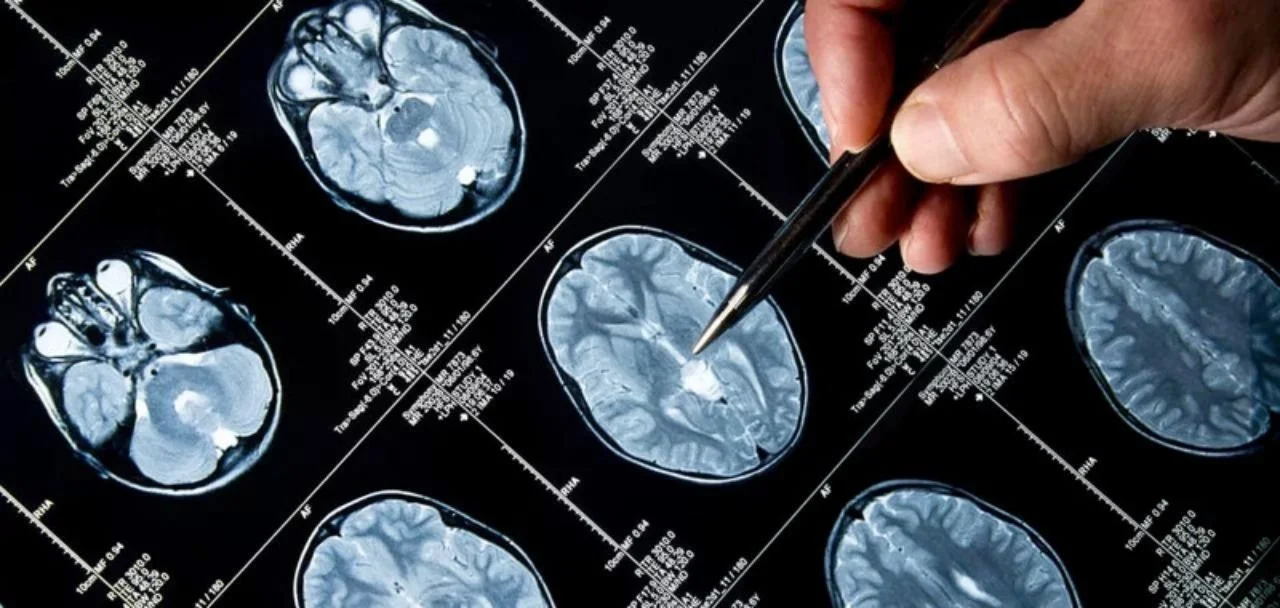

BRAIN CONDITIONS

ARTERIOVENOUS MALFORMATION

An arteriovenous malformation, which occurs most frequently in the brain or spine, is a tangle of abnormal blood vessels, causing blood to flow directly from your arteries to your veins, bypassing the surrounding tissues.

BRAIN ANEURYSM

A brain aneurysm is ballooning or bulging in a blood vessel in the brain, usually between the brain itself and the thin tissues covering the brain.

BRAIN TUMORS

A brain tumor is simply a mass caused by abnormal cell growth on or near the brain. Brain tumors can vary widely in growth rate, size, and location, and can be both noncancerous and cancerous.

CHIARI MALFORMATION

Chiari Malformation is a structural defect which results in the cerebellum, the part of the brain that controls balance and typically rests in an indention at the base of the skull, becoming displaced below the opening of the spinal canal (the “foramen magnum”).

PITUITARY TUMORS

A pituitary tumor is an abnormal growth that develops in your pituitary gland, a pea-sized glad at the base of your brain that is responsible for growth, development, and the regulation of other endocrine glands and systems.